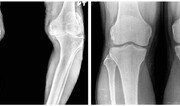

71세 여성 이모 씨는 스물한 살 때부터 밭일과 논농사를 해왔다. 여름 한낮에도 무릎을 쪼그린 채로 논밭에서 시간을 보냈다. 그렇게 50년을 지내왔다. 그러다 보니 이른 나이인 30대 후반에 무릎 통증이 찾아왔다. 통증은 시간이 갈수록 심해져 50대를 넘기면서부터는 밤에 잠을 자기 힘들 만큼 아팠다. 이 씨는 무릎 수술을 받고 싶었지만 엄두가 나지 않았다. 수술 비용 때문이다. 그랬던 이 씨가 지금은 무릎 통증이 거의 사라진 상태로 정상에 가까운 생활을 하고 있다. 지난달 양쪽 모두 무릎 수술을 받았기 때문이다. 이 씨는 대한노인회가 진행 중인 ‘저소득층 노인을 위한 퇴행성 관절염 인공관절 수술 후원 캠페인’의 도움을 받았다. 이 씨는 “수술비를 마련하지 못해 20년 넘게 극심한 무릎 통증을 안고 살아왔던 나에게 대한노인회의 인공관절 수술 캠페인은 새 삶을 살 수 있는 기회를 줬다”고 말했다. 올해 5월부터 이 같은 후원 캠페인을 시작한 대한노인회는 기초생활수급 대상자를 포함한 저소득층 퇴행성 관절염 말기 환자들에게 도움을 주고 있다. 전국의 대한노인회 245개 지회장 추천을 받은 사람도 후원 혜택의 대상이 된다. 수술을 희망하는 노인 환자는 대한노인회 보건의료사업단에 전화(1661-6595)나 우편(서울 서초구 방배로 43), e메일(ok6595@naver.com)로 신청하면 된다. 신청을 접수한 대한노인회는 환자의 경제적 사정 등을 심사해 후원 여부를 결정한다. 후원 병원의 무릎 관절 검사를 거쳐 인공관절 수술이 가능하다는 판단이 내려지면 수술에 들어간다. 이 캠페인은 2015년 4월 30일까지 계속된다. 퇴행성 관절염은 무릎을 보호하는 연골이 노화로 닳아 없어지면서 뼈와 뼈가 맞닿아 통증이 생기는 질환이다. 65세 이상 노인의 80% 정도가 이 질환을 앓고 있는 것으로 알려져 있다. 연골은 혈관이 없는 조직이다. 이 때문에 혈액 속 재생인자의 역할이 이뤄지지 않는다. 한 번 닳은 연골은 자체 회복이 되지 않는다는 얘기다. 퇴행성 관절염은 연골 손상 정도에 따라 초기, 중기, 말기로 나뉜다. 치료 시기를 놓쳐 연골이 모두 닳아 없어지는 퇴행성 관절염 말기에 이르면 걷기조차 힘들 만큼 심한 통증을 느끼게 된다. 퇴행성 관절염 말기는 약물이나 주사 치료를 하기에는 이미 늦은 시기다. 인공관절을 이식하는 수술을 통해 통증을 줄이고 무릎의 운동성을 높이는 것이 사실상 유일한 치료법이다. 수술 후에는 6개월∼1년의 회복 기간이 필요하다. 완치 후에는 등산도 가능하다. 하지만 인공관절 수술은 관절을 이식하는 큰 수술인 만큼 치료비가 만만치 않은 것이 사실이다. 건강보험 가입자라도 무릎 한 쪽을 수술하는 데만 환자 부담 비용이 250만∼300만 원에 이른다. 수술 후 입원 기간도 2, 3주여서 간병인이 필요할 수도 있어 추가 부담이 있다. 이 같은 치료비 부담 때문에 저소득층 노인들은 제대로 된 치료를 받지 못한 채 극심한 통증을 참고 견뎌야 하는 경우가 대부분이다. 건강보험에 가입하지 않았다면 환자가 부담해야 하는 돈은 두 배로 늘어난다. 의료계는 퇴행성 관절염을 앓는 노인 중 80% 정도가 수술비 부담 때문에 치료를 제때 받지 못하는 것으로 보고 있다.이종석 기자 wing@donga.com}